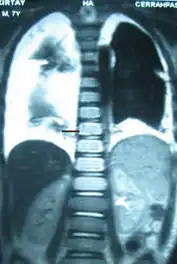

Bilateral chylothorax seen on a thoracic MRI

The cisterna chyli can be found in a thoracic MRI, making it possible to confirm chylothorax. However, MRI is not the ideal method to scan the thorax, and so it is rarely used. Another diagnostic technique is conventional lymphangiography. It is rarely used since there are equally sensitive yet less invasive techniques available to identify a chylothorax. Lymphangiography procedures use the contrast dye agent lipiodol, which is injected into the lymphatic vessels. The chylothorax shows up on the images and identifies the source any leak in the thoracic duct.[1]